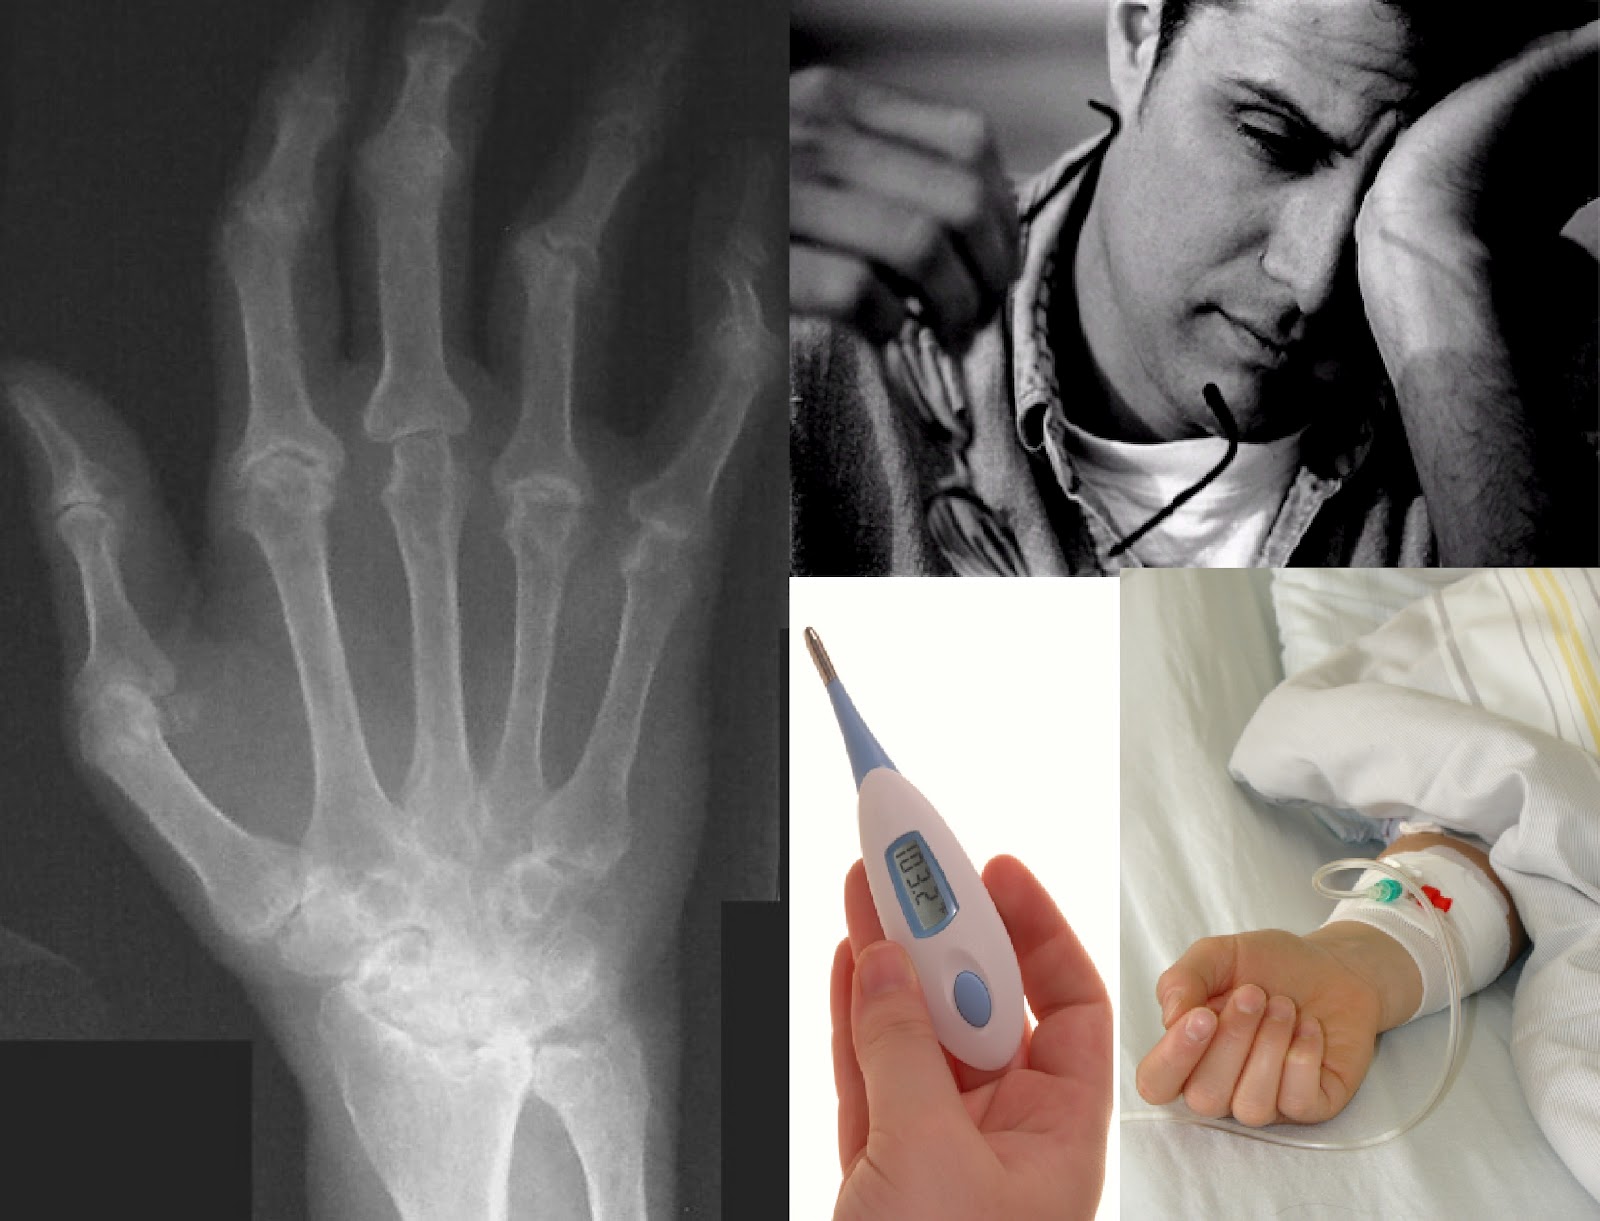

WHAT IS RHEUMATOID ARTHRITIS? Rheumatoid Arthritis (RA) is an autoimmune disease. The body’s immune system attacks healthy tissue lining the joints. ... Fetch Document

Many people think arthritis is a single disease, but it's not. Arthritis literally means "joint inflammation" and refers to a group of more than 100 rheumatic diseases and related conditions that are associated with joint pain, joint stiffness and swelling. ... Read Article

Immune-mediated polyarthritis is usually an acute (rapidly developing) process, and is very different from what is commonly called “arthritis” or degenerative joint disease. The latter is a slow degenerative process that is associated with damage to the cartilage in the joints. ... Fetch Document

AUTOIMMUNE DISEASE ALLERGIC REACTIONS